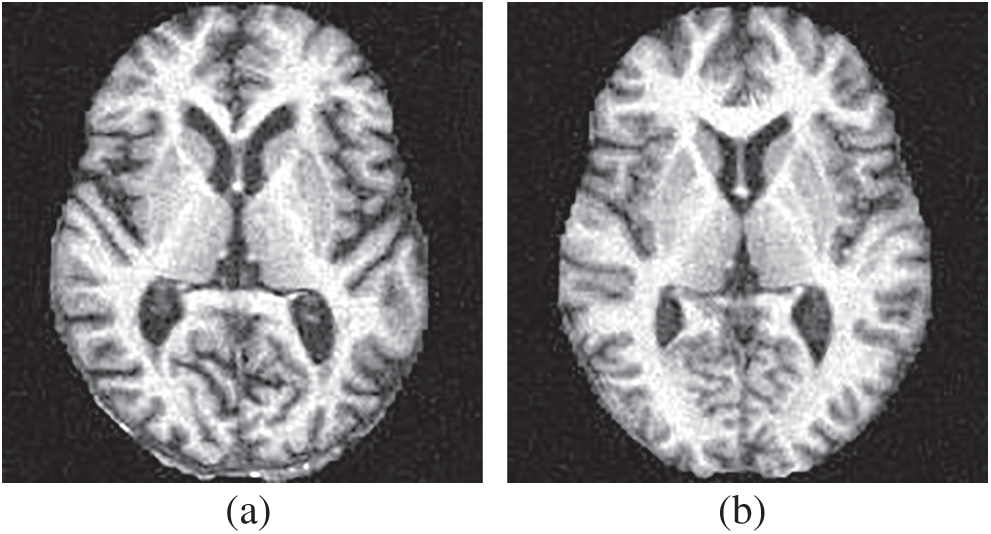

The dataset in this study was reported in Ref. [18], composed of 188 alcoholic brain images and 191 non-alcoholic brain images. Fig. 6 shows two samples of our dataset.

Figure 6: Samples of our dataset (a) alcoholism and (b) HC